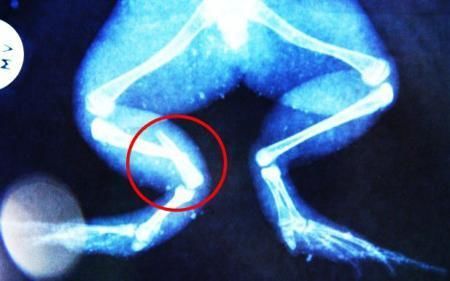

環(huán)球網(wǎng)4月2日報(bào)道 據(jù)《每日郵報(bào)》報(bào)道,上個月,南非大牛蛙布魯萊的右小腿被鄰居家的一只狗咬到,導(dǎo)致粉碎性骨折,現(xiàn)在經(jīng)過2個小時的手術(shù),它的斷腿已經(jīng)被接上,它也因此成為有史以來第一只通過外科手術(shù)用鋼針接上斷腿的青蛙。

野生生物專家安妮經(jīng)常為學(xué)校寫教材,她認(rèn)為這是人類第一次通過手術(shù)給一只青蛙接斷腿。在手術(shù)開始階段,獸醫(yī)把少量給狗用的麻醉藥注入到這只青蛙體內(nèi),讓它失去知覺。然后他在布魯萊的斷腿上切開一個小口,把一根小鋼針植入腿里。最后獸醫(yī)給它縫了9針,把切口縫合在一起。僅僅幾周后,布魯萊就能在安妮家附近活動了。這只青蛙大約已有25歲,主要以嚙齒動物、蛇和其他青蛙為食。布魯萊所屬的牛蛙種群正在不斷減小,目前只能在非洲南部的濕地里才能看到這種青蛙。